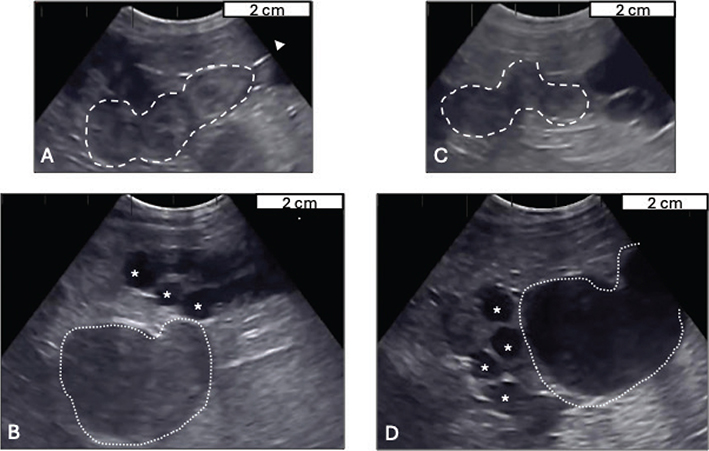

A nulliparous, 2-year Nigerian dwarf doe was evaluated for failure to conceive; doe was presented in January toward the end of normal breeding season for goats in northern hemisphere. Doe’s birth litter was quadruplets (3 females and 1 male). Doe cycled every 18-21 days throughout the breeding season and was bred by natural mating on each estrous cycle but kept coming back to estrus without any abnormal systemic health signs or concerns. Physical examination of the external genitalia did not reveal any anatomical anomaly. Vaginal speculum examination revealed a normal vaginal vault with classical rosette-shaped external cervical os. Transabdominal ultrasonography was performed with a multispecies machine (Ibex EVO III, Loveland, CO, USA); uterus was visible without intraluminal fluid with moderately distended sections compatible with uterine horns filled with anechoic or hypoechoic fluid depending on the cross section (Figure 1A, B). Differential diagnoses for a fluid-filled uterus included hydrometra, mucometra, and segmental aplasia of the uterus. Doe received 2 doses of 250 µg of intramuscular cloprostenol 10 days apart (Estrumate®, Merck Animal Health, Rahway, NJ, USA). Doe was presented for reexamination 6 days after the second dose, ~ 3 days after estrus.

Figure 1.

Figure 1. Transabdominal ultrasonographic images (obtained at 8 cm depth with 4.5-6.2 MHz probe) of the doe’s uterus at first evaluation; A. small, nonpregnant, nonfluid-filled cross sections of uterine horns (white dashed line) and B. dilated uterine tube, hydrosalpinx (white asterisks), and distended fluid-filled uterus, hydrometra (white dotted line). Similar findings were obtained on reexamination after prostaglandin F treatment; C. visible nonpregnant/nonfluid-filled sections of uterus (white dashed line) and D. persistent hydrosalpinx (white asterisks) and hydrometra (white dotted line). Images were taken at 8 cm of depth at 4.5-6.2MHz using an Ibex®eC6 multi-frequency probe

Follow-up transabdominal ultrasonography demonstrated thin-walled anechoic fluid-filled structures that narrowed to a long tube consistent with dilated uterine horns and oviducts; uterine body was visualized and did not have intraluminal fluid (Figure 1C, D).